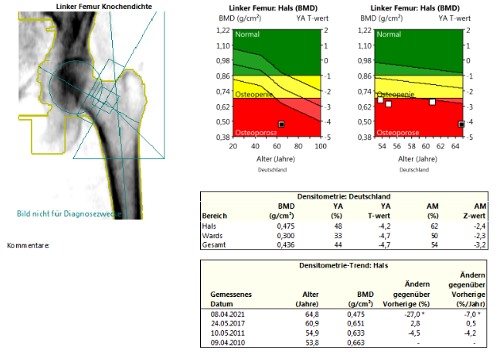

DXA + TBS:

Bei der Patientin liegt einerseits eine hochgradig reduzierte Knochenmineraldichte vor im Sinne einer sekundären manifesten Osteoporose mit multiplen atraumatischen Wirbelkörperfrakturen und andererseits zusätzlich eine

Aufgrund des sehr hohen Risikos und den aufgetretenen Spontanfrakturen unter antiresorptiver Behandlung, stellen eine Indikation für eine osteoanabole Therapie dar. Im Anschluss an diese Therapie ist jedoch eine

Konsolidierungstherapie zwingend erforderlich. Aufgrund der deutlich reduzierten Knochendichte und der anhaltenden Behandlungsindikation, würde die Patientin von einer Anschlussbehandlung mit Denosumab 60mg s.c. alle 6 Monate

profitieren.

Bei Patienten mit Malabsorption oder Malresorption sollte eine orale Bisphosphonattherapie zurückhaltend eingesetzt werden.